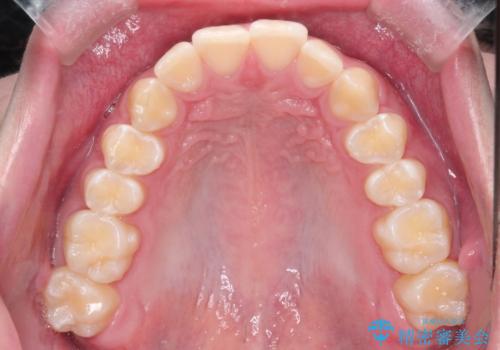

【インビザライン】短期間で出っ歯を治したい

- 出っ歯と口元の突出感が気になるということで来院されました。抜歯矯正も考えられますが、今回は早く終わらせたいという要望があり非抜歯での治療にしました。また遠方から来院されているため、来院回数のおさえられるインビザラインを選択しました。

非抜歯での治療のため、今回はスペース確保のために遠心移動とおもにIPRの処置を取り入れました。